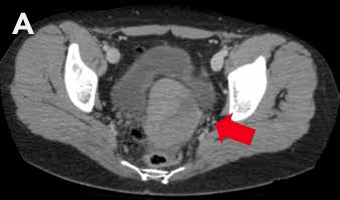

Mujer de 27 años, con antecedente de amenorrea primaria con hábito femenino, mamas Tanner V, escaso vello no terminal axilar y púbico, y que tenía pareja heterosexual y vida sexual normal. Sus exámenes hormonales demostraron testosterona en rango masculino (Tabla 1) y cariograma 46,XY compatible con insensibilidad a andrógenos. La TAC de pelvis mostró ausencia de útero, una imagen ovoidea con densidad de partes blandas de 27 mm de diámetro mayor a nivel de la bifurcación de los vasos iliacos derechos interpretada como ovario normal, y en situación anexial izquierda una masa sólida de 90 mm de diámetro mayor, bien delimitada algo heterogénea sin calcificaciones, sin liquido libre ni adenopatías (Figura 2). Fue sometida a gonadectomía bilateral 4 años antes de la consulta y la biopsia demostró un seminoma espermatocítico de 11 cm asociado a un foco de neoplasia germinal intratubular de 2 mm en la gónada izquierda y un testículo atrófico y fibroso, con epidídimo de aspecto conservado a derecha.